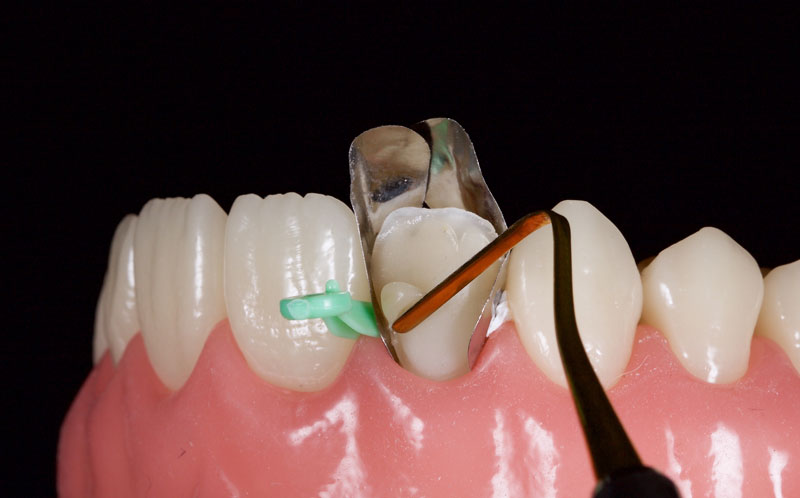

Matrices are then placed to aid the creation of contacts and an ideal emergence profile. My preference is either Mylar strips or posterior matrix bands (e.g., Paladent or Garrison) placed on end (Fig. 9).

These can be anchored with Teflon tape or conventional plastic wedges. A dentin (medium opacity) resin is placed to block out light transmission and maintain the restoration’s value in comparison to the surrounding tooth structure. This should be under contoured facially.